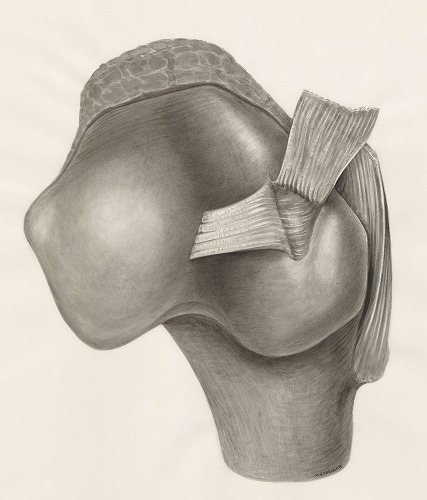

複雑な材料挙動・機械特性を精度よくシミュレーションする高度な技術力と、 ソースプログラム保有により顧客ニーズに応じたカスタマイズ対応が可能です。